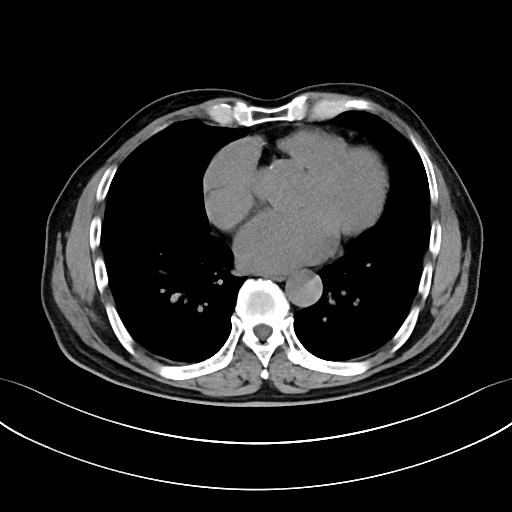

下图的胸部CT平扫,有什么大问题?

图4

仔细一看,主动脉里面有线样高密度阴影!这个要高度警惕主动脉夹层!

图5